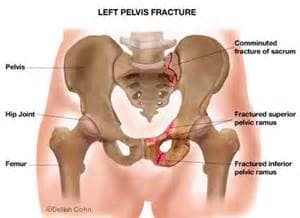

Cuando hay dolores de espalda baja (en la parte lumbar) es tambien imprecindible asegurase que el dolor no venga ni sea provocado por la pelvis. Muchas veces el sacroiliaco puede dar sintomas en las mismas zona de las articulaciones lumbares, hasta incluso en algunos casos radiando hasta la rodilla por la parte trasera. En otros casos una rotacion inapropriada de la pelvis hacia un lado puede crear muchos problemas en la base de la columna y ser la verdadera causa de la inflamacion: si no se recoloca la pelvis en su sitio no habra’ intervencion en la lumbar que vaya a ser duratura y efectiva.